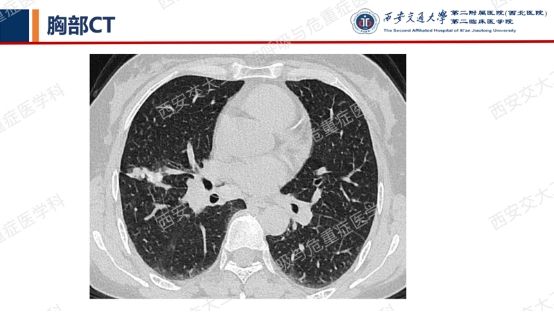

患者呼吸道症状并无太多特异性,还是从影像资料入手,右肺中叶外侧段高密度灶并纵隔及右肺门淋巴结肿大,同时存在双肺多发囊性病变,一元论?多元论?

患者实验室常规检查项目无明显异常,结核感染T淋巴细胞:测定管-阴性对照管1685.11pg/mL,阳性(+)PPD试验++;肿瘤标志物阴性。当我们无法肉眼一下子看穿疾病本质,一定要根据病情启用呼吸科第三只眼睛——支气管镜。针对右肺中叶外侧段病灶行EBUS-TBLB,病理回报“慢性炎并灶状碳末沉积”;针对纵隔、肺门肿大淋巴结行EBUS-TBNA,4R组病理回报“慢性肉芽肿性炎伴灶状坏死”,加做TB-DNA阳性。继发性肺结核并纵隔淋巴结结核诊断明确,但双肺多发囊性病变用结核难以解释。

囊性病变常要鉴别的疾病包括我们第一期的BHDLAM,还有LIP(淋巴细胞性间质性肺炎)、PLCH(肺朗格汉斯组织细胞增多症)、PLCDD(肺轻链沉积病)等。该患者囊性病变特点:沿支气管血管束周围分布,多个囊有血管贴边或穿行于囊肿壁。追问患者有口干不适,进一步行SS-A 52 101.65 AUSS-A 60 47.30AUANA 阳性(+),滴度1:10000 阳性(+),又经唾液流率、泪液流率、唇腺活检及风湿免疫科会诊,诊断干燥综合征。